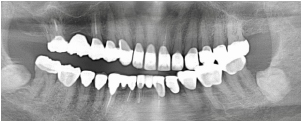

治療前のレントゲン

治療後のレントゲン

主訴は上の前歯の根元に違和感があるとのことでした。レントゲンを撮影したところ左上の2番目の歯の根元に大きな膿の袋が出来ており、保存不可能と診断、抜歯してジルコニアブリッジで治療することになりました。以前治療されていたセラミック冠の見た目も気になるとのとでした。問題のある根管治療はすべてやり直し、ファイバーコアを入れてから上下6歯をジルコニアオールセラミックで治療しました。ハグキの色も健康的になりました。